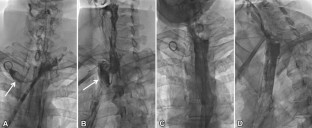

Fig. 1